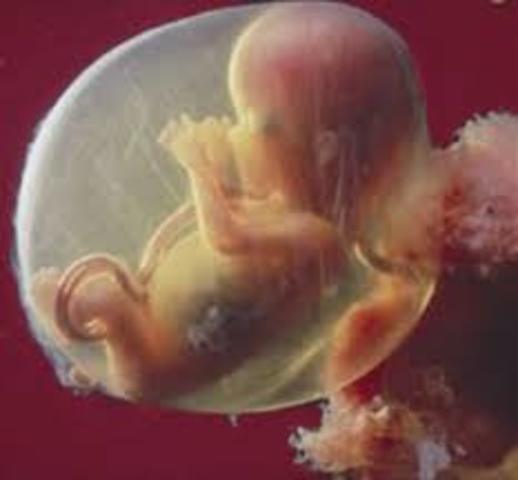

• semana 12

semana 12

En la etapa fetal el crecimiento es notable. En la novena semana el feto pesa 8 gramos y al momento de nacer alcanza un peso de 3000g aprox. La cabeza sigue muy grande aunque el tronco sigue creciendo poco a poco de tamaño, la región pélvica se mantiene estrecha.